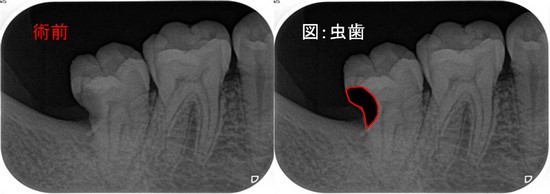

【症例】智歯による第2大臼歯遠心カリエス

(EEデンタルブログより引用)

?毎度おなじみのエアースケーラー用チップを使用してチマチマ削ります。

(カボ・ナカニシのダイヤル調整型を使い、パワー設定は基本2で使用してください)

カリエス除去後まず、遠心をレジン充填(隔壁)。フロアブルレジンを使用。

? 削った時点で神経が見えており、出血がなく、神経が死んでいるのが確認できたので、次に根管治療を行います。

? この歯は樋状根でした。根管治療後、レジンコア+レジン充填にて修復を行いました。